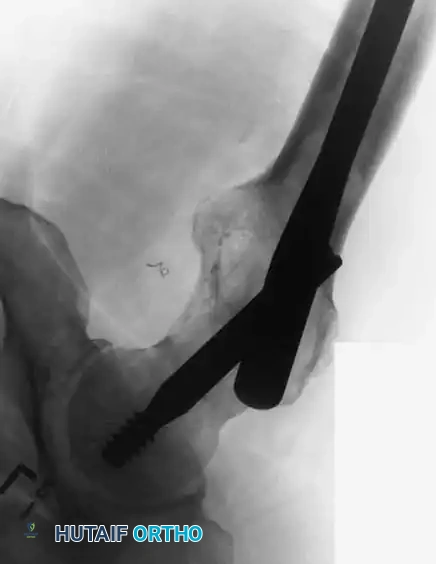

5. Proximal and Distal Locking:

* Proximal fixation is achieved with a large lag screw directed into the center of the femoral head, providing rotational stability and preventing varus collapse of the proximal femur.

Lateral fluoroscopic view confirming the central placement of the cephalomedullary lag screw within the femoral head and neck.